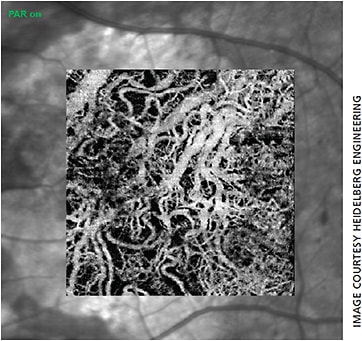

Heidelberg says the multimodal Spectralis offers the ability to combine OCTA with structural OCT, confocal scanning laser imaging and dye-based angiography in a single device.2 The 10° x 10° OCTA images have a lateral resolution of 5.7 µm/pixel to resolve the fine capillary network and an axial resolution of 3.9 µm/pixel for segmentation of the four histologically-validated retinal vascular plexuses.3 These include the nerve fiber layer plexus in addition to the superficial, intermediate and deep capillary plexuses.

“The superficial vascular complex is particularly useful for visualizing retinal vascular diseases such as diabetic retinopathy and retinal vein occlusion,” Dr. Brown says. “It allows you to easily see capillary dropout to assess why a patient’s acuity may be reduced and determine the visual prognosis.”

The deep vascular complex, which consists of the intermediate and deep capillary plexuses, is more finely tuned towards AMD. “Segmentation allows for viewing of the foveal avascular zone and macular capillaries that would otherwise be obscured by the superimposed layers with FA,” Dr. Brown says. “Although OCTA is improving logarithmically, the deeper layers are still prone to projection artifacts that make pathology harder to differentiate.” The Spectralis OCT offers TruTrack Active Eye Tracking, which prevents motion artifacts to ensure high quality images. Additionally, a projection artifact removal tool utilizes information from the superficial vascular plexus to remove artifacts via post processing for better views of the outer retina.4